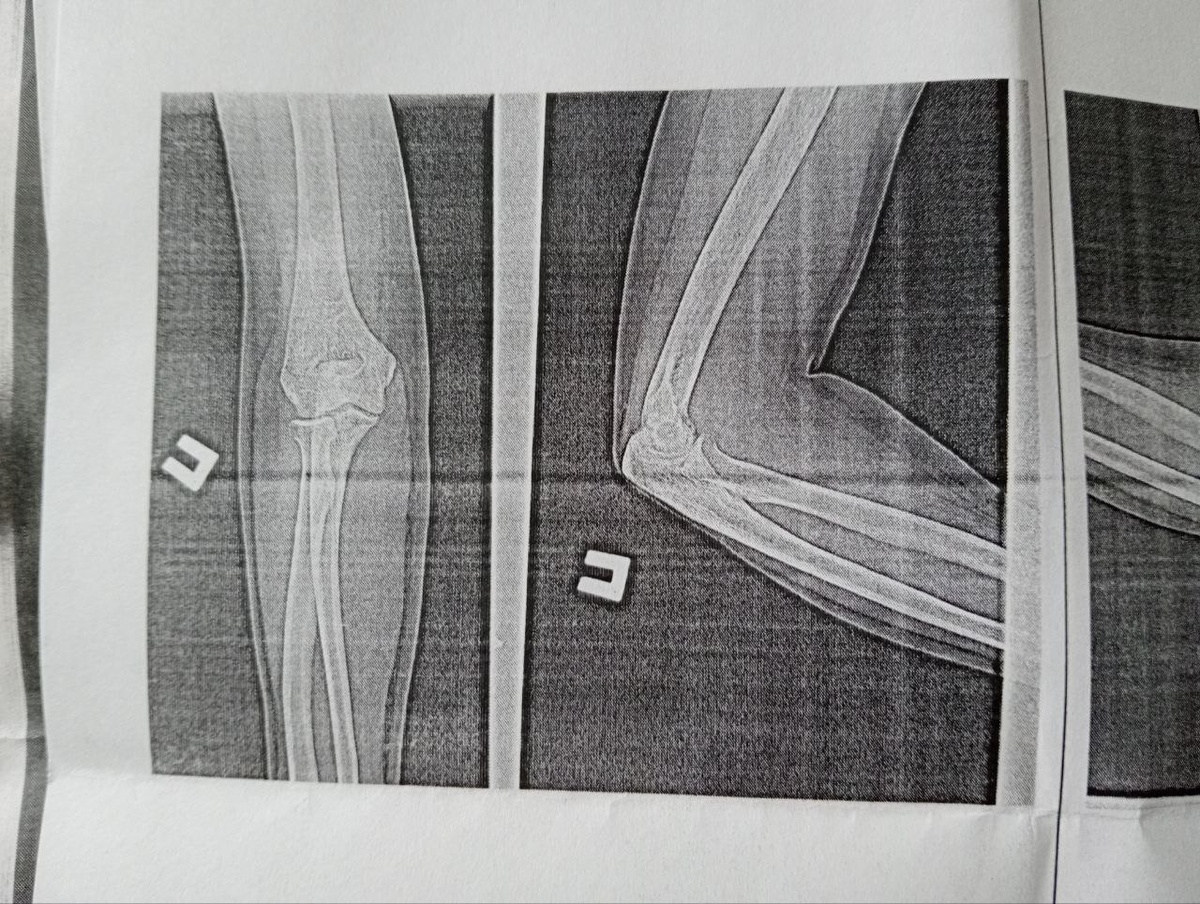

Остеоартроз локтевых суставов подтвердился

При чем обоих локтей на снимке и в заключении рентгенолога. Теперь хоть будет что предъявлять ревматологу или ортопеду. Даже растерялась, к кому теперь идти...

Красивые косточки )) Снимок локтевых суставов